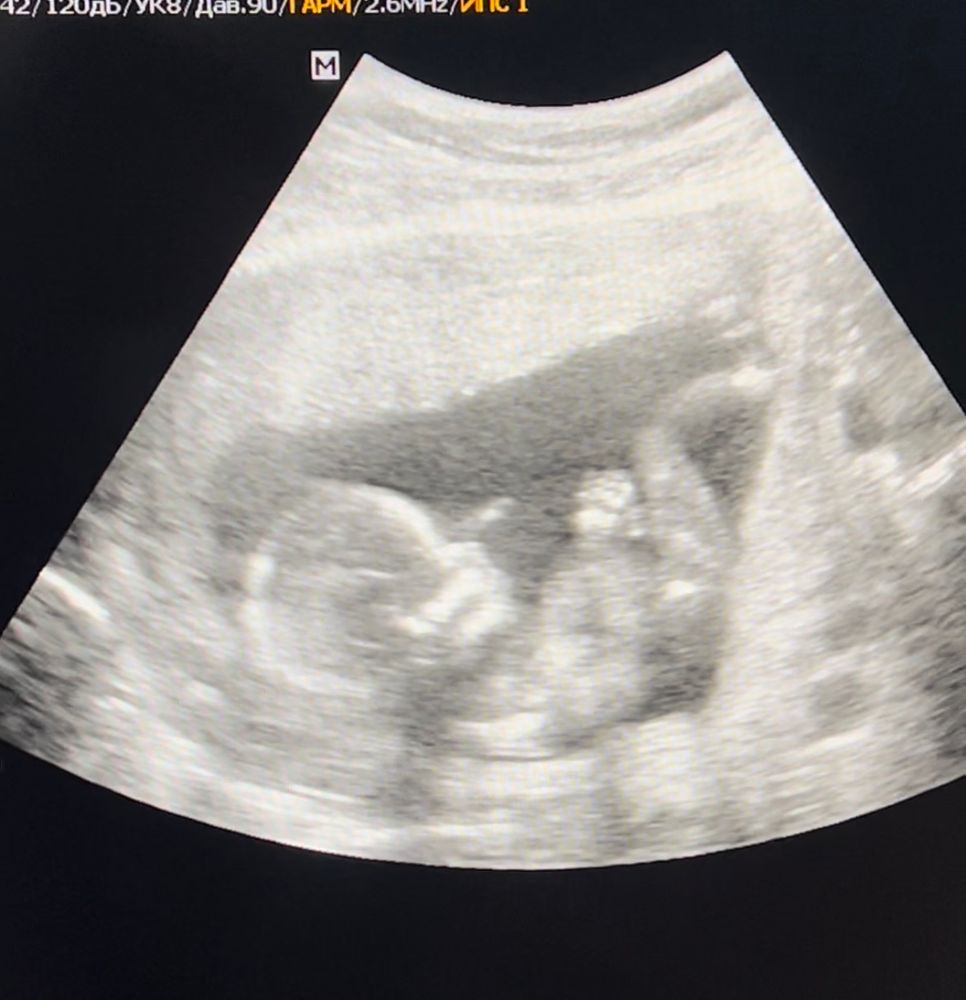

Пол малыша 🥰

Катэ, сказал что ничего не понятно и точно сказать не смогут, это узи с 13 недель )

Диана, здесь вам тоже ничего не скажут ибо полового бугорка на фото нет.

Катэ, лично мне показалось что ножка (стопа) большая, скорее всего мужская 😅

Алина, это узи с 13 недель) сказали что очень непонятно и пока ничего говорить не будут, дабы не вводить в заблуждение

Мне почему-то парень видится)))))

Наталья, и нам также ))